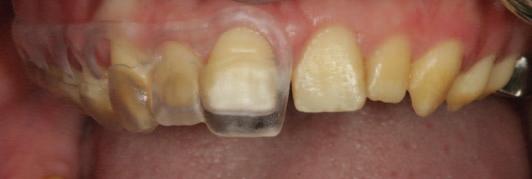

FIGURE 3: A pre-operative radiographic assessment and clinical try-in of the surgical guide gives the clinician an indication of the extent of crown lengthening surgery required. The clinician may confirm that sufficient crown–root ratio, distance from furcation anatomy, keratinised tissue, and attached gingivae will remain post surgery, and ensure the complete and comfortable seating of the guide at this stage. It is of note that the stainless steel crown on tooth UR6 was lost to retention failure between the radiographic assessment and the clinical assessment in this case.

n Following clinical and radiographic assessment of the width of the keratinised mucosa, the positioning of the gingival margin in relation to the cemento-enamel junction (CEJ) and the distance of the CEJ from the bone crest, the surgical guide is tested for stability and the proposed gingival margins are approved ( Figure 3 ). To achieve an optimised outcome, the operator should envisage that at least 2mm of keratinised tissue, including at least 1mm of attached gingivae, remain intact post surgery.4 A favourable crown–root ratio and integrity of furcation anatomy must remain intact post surgery.